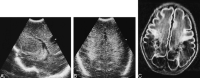

Background and purpose: In the early 1980s, diagnosing periventricular leukomalacia (PVL) in neonates by using cranial sonography was possible for the first time. Our purpose was to investigate the possibility of diagnosing PVL in the acute stage by using MR imaging. We evaluated early MR features of hypoxic-ischemic brain injury in neonates with periventricular densities (flares) on cranial sonograms to determine the added value of MR imaging over sonography alone for early diagnosis of brain damage.

Results: Fifty infants were classified according to the highest sonographic grade up to the day of MR imaging: 23 infants had sonographic grade 1 (flares < 1 week), 15 had sonographic grade 2 (flares > or = 1 week), four had sonographic grade 3 (small localized cysts), and eight had sonographic grade 4 (extensive periventricular cysts); none had sonographic grade 5 (multicystic leukomalacia) on the day of MR imaging. Overall, the additional information provided by MR imaging (over sonography alone) consisted of the depiction of hemorrhagic lesions in 64% of the infants. Extent and severity of the hemorrhages varied from isolated punctate lesions to extensive hemorrhages throughout the white matter; the latter were followed by cystic degeneration at autopsy in two infants. In nine of the 12 infants with cystic PVL, MR images showed more numerous or more extensive cysts. In addition, in two infants, MR images showed cysts not present on sonograms. In 32% of the infants, MR imaging provided no additional information; in these children, all but one had flares on sonograms whereas MR images showed no abnormalities or a zone of mild periventricular signal change.

Conclusion: MR imaging can depict the precise site and extent of hypoxic-ischemic brain injury at an earlier stage and allows a wider differentiation of lesions as compared with sonography alone. Hemorrhagic PVL is considered to be rare, but was present in 64% of our study population.